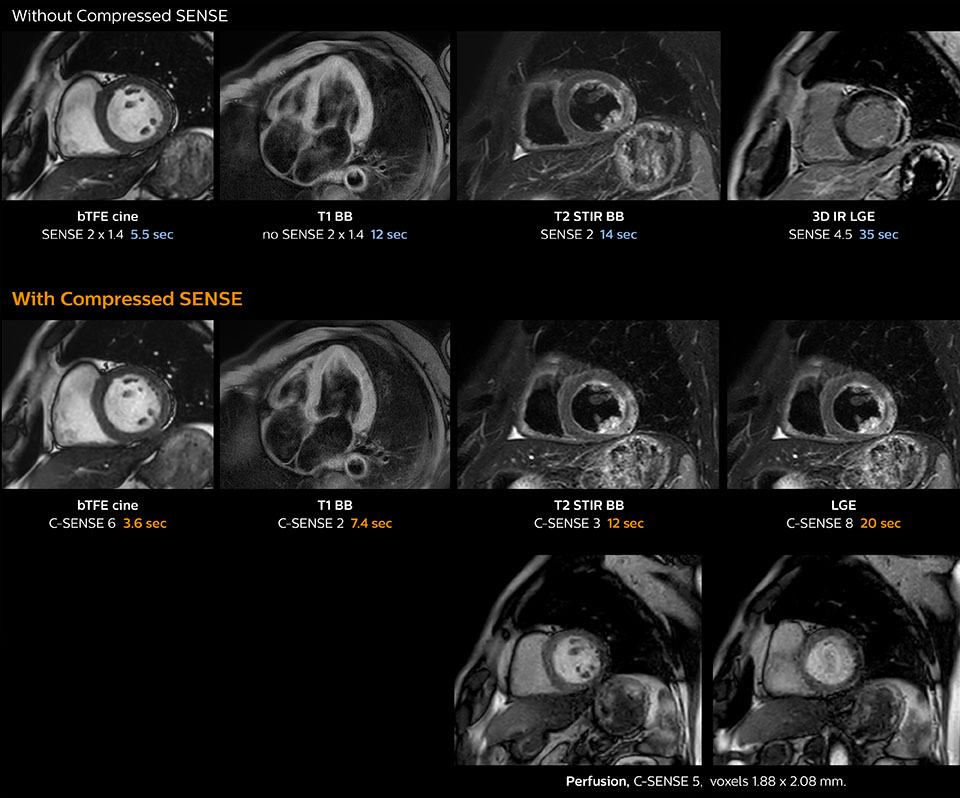

“Compressed SENSE has now been implemented in all cardiac exams. Thanks to the acceleration, fewer breath holds are now needed, or breath hold times are shortened. This reduces the burden of the exam for cardiac patients, without affecting the quality of information required for cardiac function analyses,” he says. “Because it’s easier for patients to comply with the breath hold times” “In our previous cardiac cine sequence, we were acquiring two slices during one breath hold. With Compressed SENSE, we increased this to four slices per breath hold. It is also possible to shorten scanning time using a C-SENSE factor 6 without sacrificing image quality.”

Dr. Koshi Miyake, cardiologist, explains that scanning of patients with cardiac arrhythmia can be challenging, as scanning times can become very long due to the varying heart rate. So his most important motive to implement Compressed SENSE in cardiac MRI exams was to reduce the burden of breath holds for the patient, while maintaining high image quality. He hopes this can also help to reduce motion caused by the difficulty for patients to hold their breath.

“Typically, in scans with high contrast, such as 2D balanced TFE cine, a quite high C-SENSE factor may be used. When we tried a higher C-SENSE factor, we saw still no significant influence on cardiac ejection fraction, but 2D image quality started to decline. For coronary imaging, we use a C-SENSE factor of 3 in 3D balanced TFE, or even up to 4 when contrast is high.”

These images of a patient with acute myocardial infarction images were acquired on Ingenia 1.5T with and without Compressed SENSE.

These images with and without Compressed SENSE were acquired on Ingenia 1.5T.